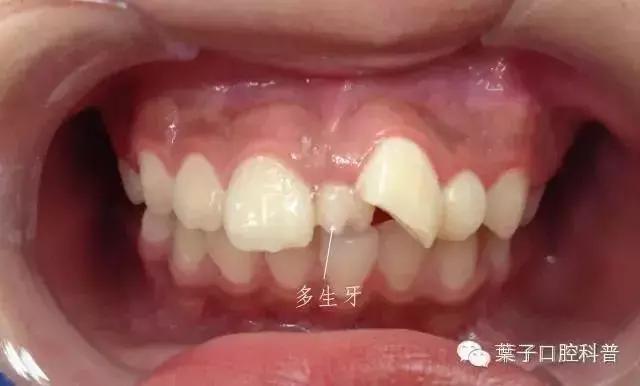

照片可以看到,孩子的侧切牙已经长了,但上门牙还呈外"八"字,门牙之间缝隙很大。

医生给小女孩进行了常规检查后拍X线片,结果发现:有多生牙,而且是两颗。

多生牙 —— 顾名思义,就是多余长出来的牙齿,最常见的是上颌“正中多生牙”,也就是长在门牙之间的牙齿。

一般来说,单侧或对称都有可能生长,有的已经萌出,有的会埋伏阻生,有的甚至会倒着长。多生牙一般是小锥形,牙根较短。

上述案例中小姑娘的多生牙是属于埋伏生长。还有一种情况是,“长出来”了的多生牙。